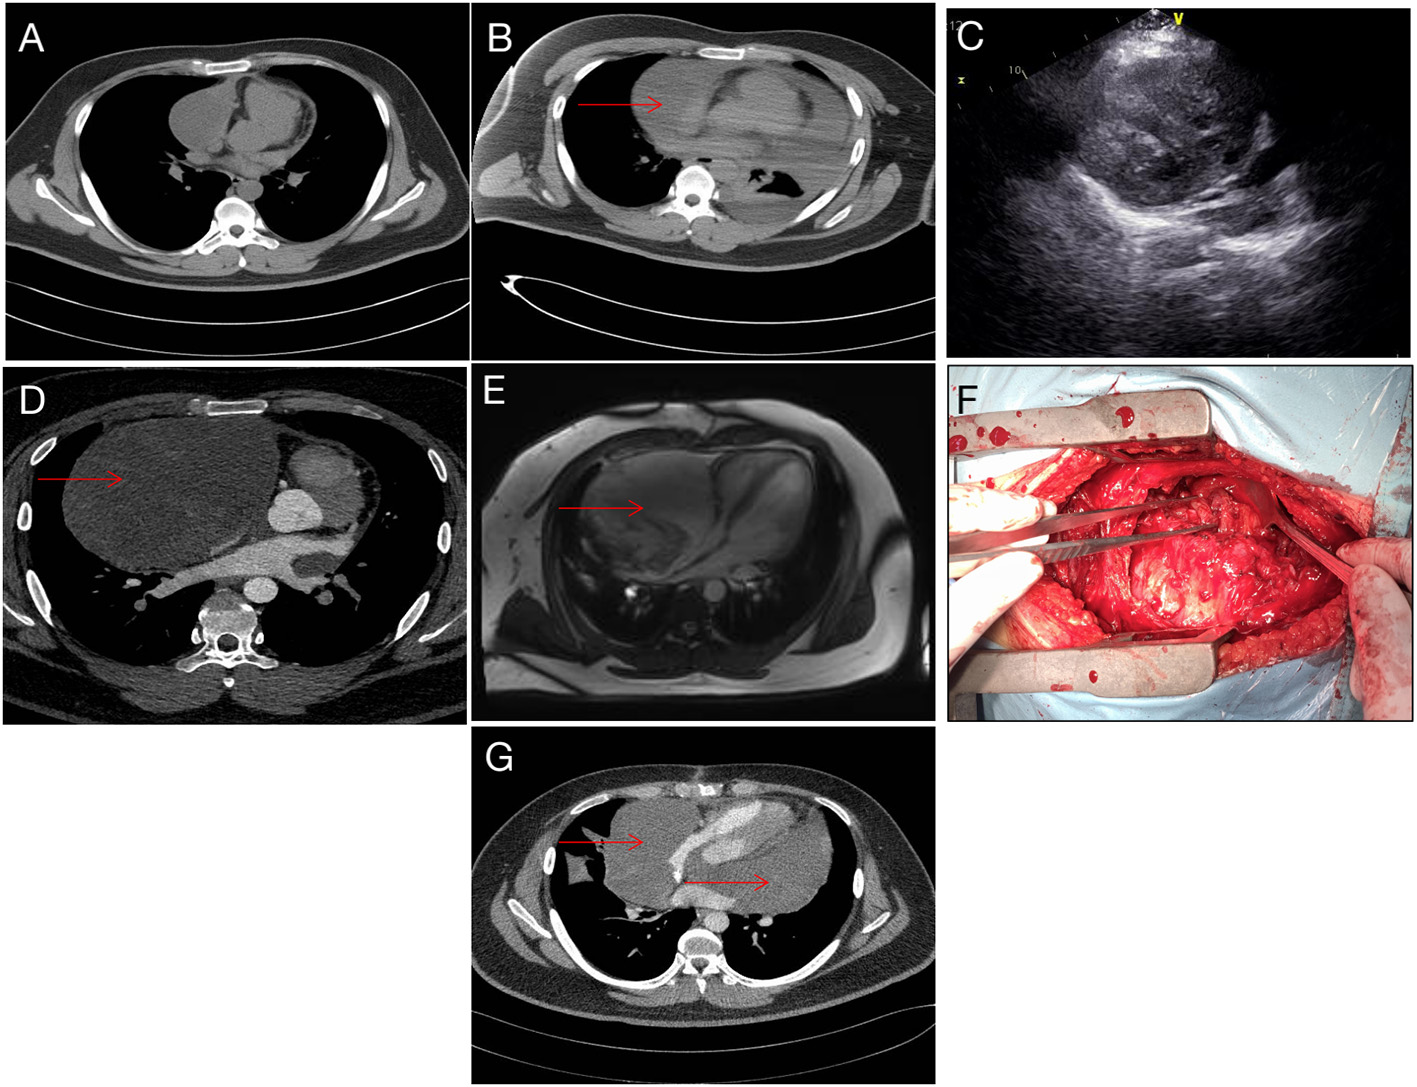

A 19-year-old man was referred to our hospital for the first time because of chest tightness and dyspnea. Chest echocardiography and computed tomography (CT) revealed a large amount of pericardial effusion, pleural effusion, left lung swelling, and right lower lung swelling (Figure 1A). The patient was subjected to pericardiocentesis and drainage; the drained fluid was sent for pathological examination. The pathology report revealed a lack of tumor cells (Figure 2A); acid-fast staining of the sample was also not positive for Mycobacterium tuberculosis (Figure 2B). The patient was also subjected to bone marrow puncture; however, the biopsy sample did not show any positive results. Following pericardiocentesis and treatment aimed at providing symptomatic relief, his pleural effusion and pericardial effusion were absorbed (Figure 1B). He was then discharged after symptom improvement. Therefore, some special manifestations of patients have been ignored. Although a mediastinal mass was noted in the first CT images, the pathological examination and related auxiliary examinations of pericardial effusion did not discover any positive results (Figure 1B). Five months later, the patient was re-examined at the local hospital and was found to have a pericardial mass through echocardiography and chest CT.

Figure 1

Imaging data. (A) CT image taken during the first admission. (B) After pericardiocentesis, CT indicating a suspicious mass (red arrow). (C) Echocardiography showing pericardial space-occupying lesions. (D) Reexamination after 5 months showed obvious space occupation (red arrow). (E) Preoperative magnetic resonance imaging, right pericardium, showing a cystic mass (red arrow). (F) During the operation, the tumor filled the pericardial cavity. (G) Tumor recurrence noted 5 months after operation (red arrow).

Then the patient had seen a doctor again for further treatment. Echocardiography, CT, and nuclear magnetic resonance imaging (MRI) at our hospital indicated that the right anterior mediastinum mass had compressed the right heart (Figure 1C) and the aortic root; it measured 15.3 × 11.7 × 15.1 cm (Figures 1D,E). He had no family history relevant to cardiac complaints. Following relevant preoperative examinations, he underwent mass resection via a median sternum incision. The size of the mass was about 20 × 15 × 19 cm (Figure 1F). The mass was found to completely cover the right atrium, superior and inferior vena cava, ascending aorta, and part of the pulmonary artery; it also partly covered the anterior wall of the right ventricle. After the operation, pathological examination (Figures 2C–E); furthermore, an SS18 gene test was done (Figure 2F). It was found that the SS18 gene was broken, so the result was positive, suggesting SS. A postoperative echocardiography performed 2 months after discharge demonstrated a heterogeneous hypoechoic lump in the pericardium; thus, tumor recurrence was considered. After 2 months of treatment with traditional Chinese medicine, he was referred to our hospital again. CT angiography revealed a more significant layer of cystic consolidation on the left margin of the heart that measured about 12 × 6.9 cm (left), 11.5 × 5.6 cm (right) (Figure 1G). Thus, following discussion with the patient, chemotherapy was initiated. The patient is currently undergoing chemotherapy with regimen at the oncology department of our hospital.